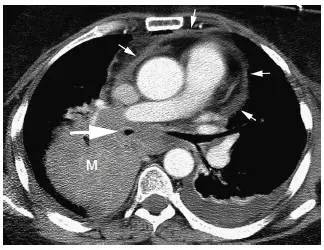

图11 小细胞肺癌

对比增强CT 显示肺门巨大肿块(M),肿瘤包绕并使中间段支气管狭窄( 大箭头),并延伸至隆突下间隙内,局部浸润引起心包增厚( 小箭头),左侧可见胸腔积液